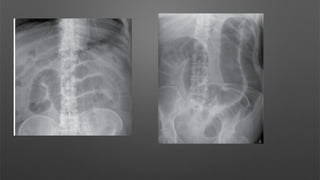

This is a supine AP abdominal radiograph

The pubic symphysis is included on this radiograph,

however the hemi diaphragms are not visualised.

Ideally I would like to see both hemi diaphragms.”

A: “There is no evidence of free gas.”

B: “There are multiple centrally located gas filled

‐

loops of bowel

Valvulae conniventes are seen in many of the loops

and they measure >3cm in diameter in keeping

with dilated loops of small bowel.”

C: “There is no abnormal calcification.”

D: “There is no fracture or bony abnormality.”

E: “There is no evidence of previous surgery,

medical devices or any foreign body.”

Impression

This is an abnormal abdominal radiograph showing

dilated loops of small bowel.